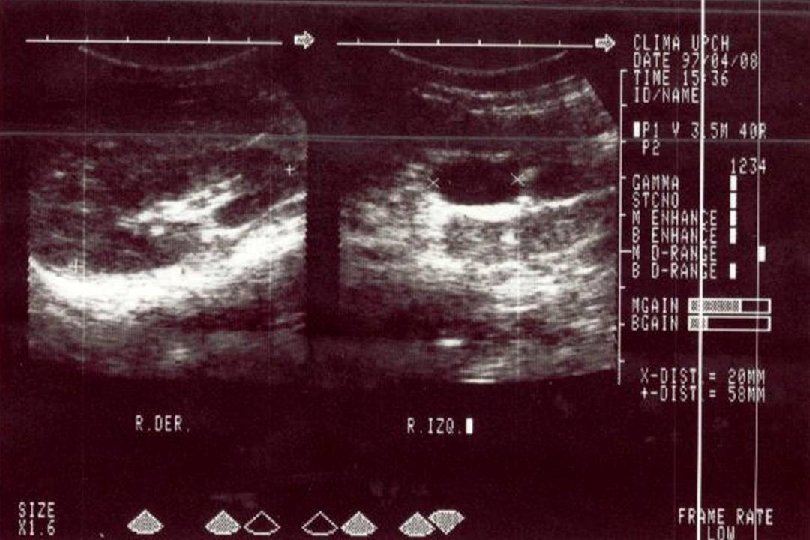

SECUENCIA DE IMAGEN o ECOGRAFIA. o CISTOURETROGRAFIA RETROGADA POST MICCIONAL. o PIELOGRAFIA ENDOVENOSA o GAMMAGRAFIA RENAL CON DMSA-TC 99. o RADIORENOGRAMA o UROGRAFIA POR RMN o TAC HELICOIDAL o ENDOSCOPIA VIRTUAL